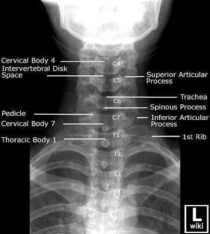

Las radiografías, generalmente llamadas rayos X, producen imágenes como sombras de huesos y ciertos órganos y tejidos. Las radiografías son muy buenas para detectar problemas óseos. Pueden mostrar algunos órganos y tejidos blandos; sin embargo, la MRI y la CT suelen crear mejores imágenes de los mismos. Aun así, las radiografías son rápidas, fáciles de obtener y menos costosas que los otros estudios, por lo que se pueden usar para obtener información rápidamente.

Un tubo especial dentro de la máquina de rayos X emite un haz de radiación controlada. Los tejidos del cuerpo absorben o bloquean la radiación en diferentes grados. Los tejidos densos como los huesos bloquean la mayor parte de la radiación, pero los tejidos blandos, como la grasa o los músculos, bloquean menos radiación. Después de pasar por el cuerpo, el haz alcanza una pieza de un fragmento de película o un detector especial. Los tejidos que bloquean altas cantidades de radiación, como los huesos, aparecen como áreas blancas en un fondo negro. Los tejidos blandos bloquean menos radiación y aparecen en tonos de gris. Los órganos que contienen principalmente aire (como los pulmones) aparecen en negro. Los tumores son por lo general más densos que el tejido que los rodea, por lo que suelen verse en tonos grises más claros.